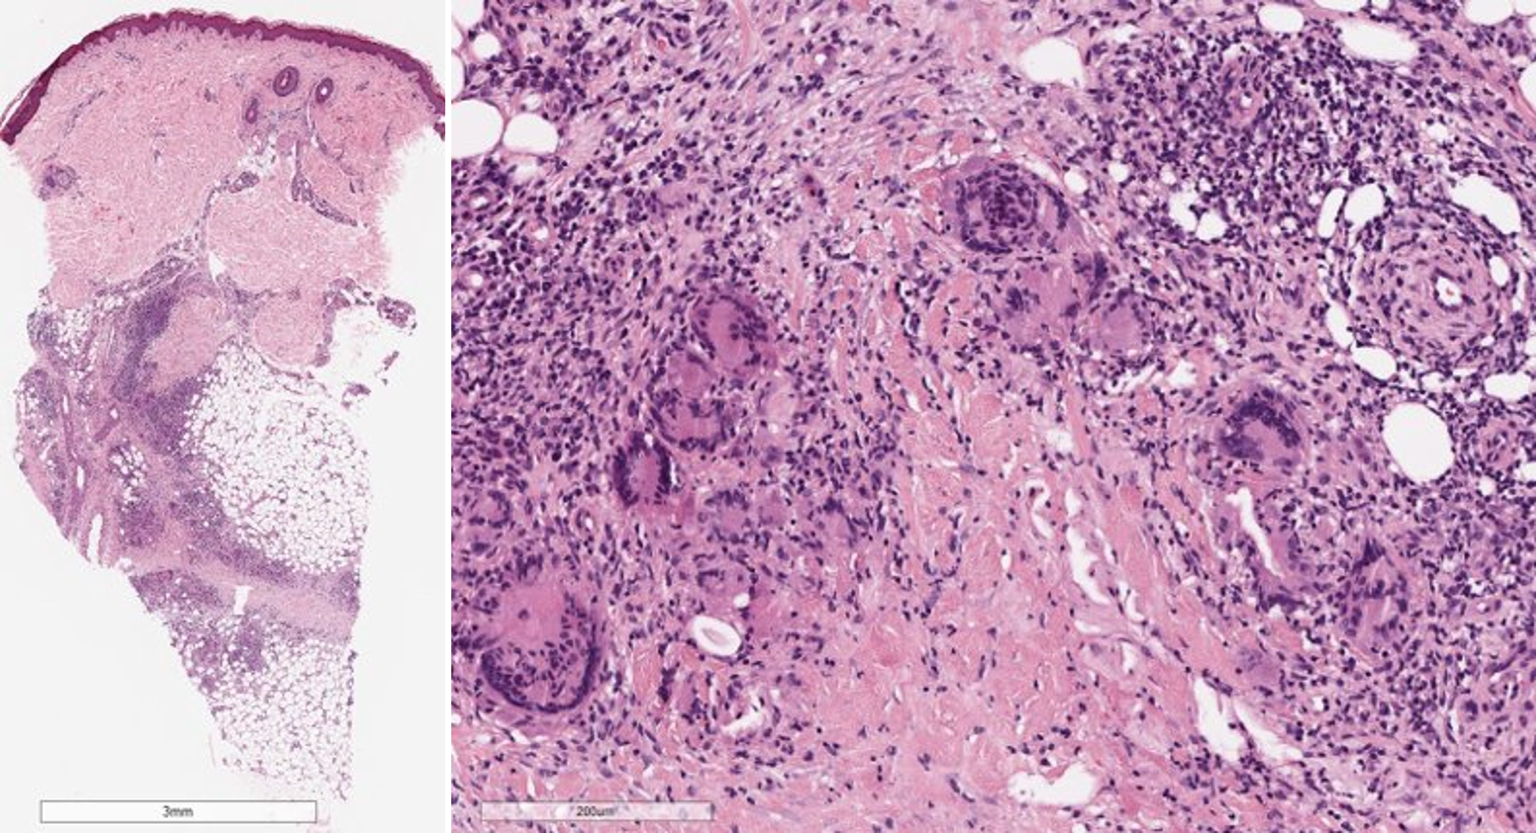

Abb. 2

Histologisches Bild eines Erythema nodosum mit septaler Pannikulitis (Hämatoxylin-Eosin-Färbung): Das entzündliche Infiltrat ist vorwiegend auf die verdickten und fibrotischen Septen der Subkutis beschränkt. Das entzündliche Infiltrat ist überwiegend lymphozytär mit einer Beimischung von eosinophilen Granulozyten, Plasmazellen und vielen vielkernigen Riesenzellen. Die Gefäße sind unauffällig

Histopathologie

Die Histologie wird charakterisiert durch eine septale Pannikulitis ohne begleitende Vaskulitis. Die Zusammensetzung des entzündlichen Infiltrates ändert sich im Verlauf: Im Initialstadium zeigt sich im Korium ein schütteres perivaskuläres lymphozytäres Infiltrat, im Bereich des Fettgewebes zeigen sich septal und paraseptal Infiltrate neutrophiler Granulozyten mit einer Verbreiterung der subkutanen Septen durch das Ödem. Das Vollbild ist gekennzeichnet durch perivaskuläre und im Fettgewebe überwiegend septale histiozytenreiche Infiltrate mit Beimengung von Riesenzellen und neutrophilen Granulozyten. In der Subkutis finden sich durch fibrotischen Umbau verdickte Septen. Charakteristisch sind die sog. Miescher-Radiärknötchen, hierbei handelt es sich um paraseptale Granulome mit mehrkernigen histiozytären Riesenzellen (Abb. 2; [26]).

Merke

Das Erythema nodosum ist eine septale Entzündung des subkutanen Fettgewebes ohne begleitende Vaskulitis. Spezifisch ist der Nachweis von Miescher-Radiärknötchen.